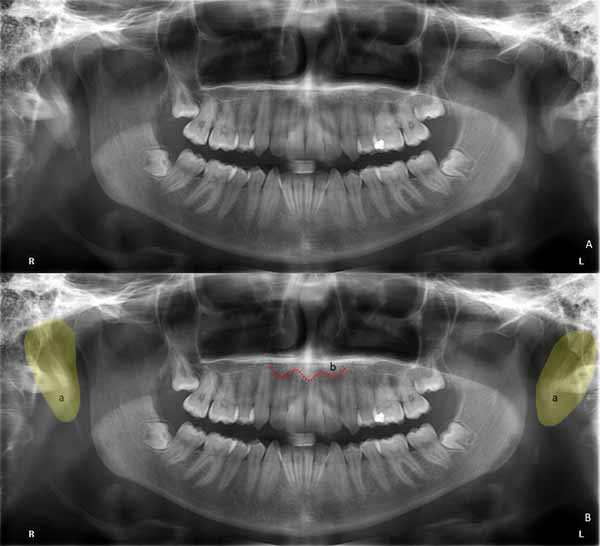

パノラマX線画像における軟部組織構造と気道

軟部組織は、パノラマ画像では拡散したエックス線不透過性の影として描写されます。

デンタルX線写真と同様に、上顎切歯より上方に描かれた鼻の軟組織部分の輪郭を見ることができます。また、外耳は頸椎と頸椎枝の間に丸みを帯びた、わずかにエックス線不透過性の構造体として描かれていることもわかります(画像28を参照)。

(a)外耳の輪郭

(b)鼻の軟部組織

舌は、上顎と下顎の両方に広がる、大きなドーム型のエックス線不透過性構造として描かれています。舌の根元では、喉頭蓋が両側から画像化されているのがわかります(画像29を参照)。パノラマ画像で区別できる他の軟部組織構造としては、軟口蓋と鼻甲介があります(画像29を参照)。

上気道は、パノラマ画像ではよりエックス線透過性の高い領域として描写されます。これらは気管、口腔、鼻腔から構成されます(画像29を参照)。経験の浅い検査官は気道を病理学的変化や骨折と誤解することがあるため、X線画像で気道を認識して区別できることが重要です。

(a)舌

(b)軟口蓋

(c)下鼻甲介

(d)中鼻甲介

(e)喉頭蓋

(f)頭頸部気道